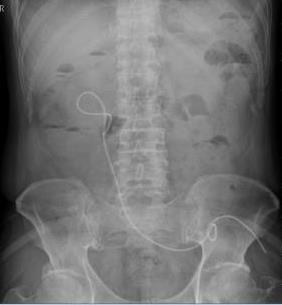

摘要:目的 探讨软式内镜辅助逆行性输尿管导管置入术,对Bricker回肠膀胱术后,输尿管回肠吻合口狭窄即刻再通的疗效。方法 回顾性分析2016年11月-2022年10月该院收治的17例Bricker回肠膀胱术患者的临床资料,共28处输尿管回肠吻合口狭窄,均行软式内镜辅助逆行性输尿管导管置入术治疗。结果 所有患者的总手术时间均 < 50 min。经内镜治疗成功再通的有21处。中位住院时间为6(4.75,8.50)d。28处输尿管回肠吻合口狭窄中,21处内镜下即刻再通成功(左侧10处,右侧11处),7处内镜下即刻再通失败(左侧4处,右侧3处)。21处内镜下即刻再通成功包括:单纯性逆行性置入输尿管导管15处,内镜下输尿管回肠吻合口扩张、网篮取石和逆行性支架置入1处,超细内镜下逆行性输尿管支架置入术3处,十二指肠镜下逆行性输尿管支架置入术2处。17例患者,输尿管支架尿液引流通畅,代膀胱回肠及输尿管回肠吻合口均有不同程度擦伤和少量出血,未发生迟发性出血、穿孔、严重泌尿系感染、支架堵塞和移位等严重并发症。结论 软式内镜辅助逆行性输尿管导管置入术,对输尿管回肠吻合口狭窄的即刻再通,安全且有效。值得应用于临床。